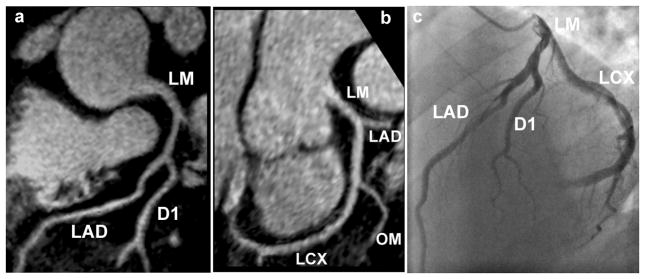

Figures 7a and 7b show reformatted coronary artery images from a 39 year old male patient acquired with the radial EPI technique. Long segments of the LM, LAD, and LCX are well depicted. No significant stenosis was found in this case and the coronary MRA images correlate well with the x-ray angiography image (Fig. 7c). Figure 8 shows coronary artery images from a 74 year old female patient illustrating the detection of significant stenoses in the distal LCX (shown as white arrow) and total occlusion of the LAD. Once again there is excellent correlation between the radial EPI coronary MRA technique (8a) and x-ray angiography (8b).

Figure 7.

Reformatted coronary artery images (7a and 7b) from a 39 year old male patient acquired with the radial EPI technique. No significant stenosis was found in this case and the coronary MRA images correlate well with the x-ray angiography image (7c).